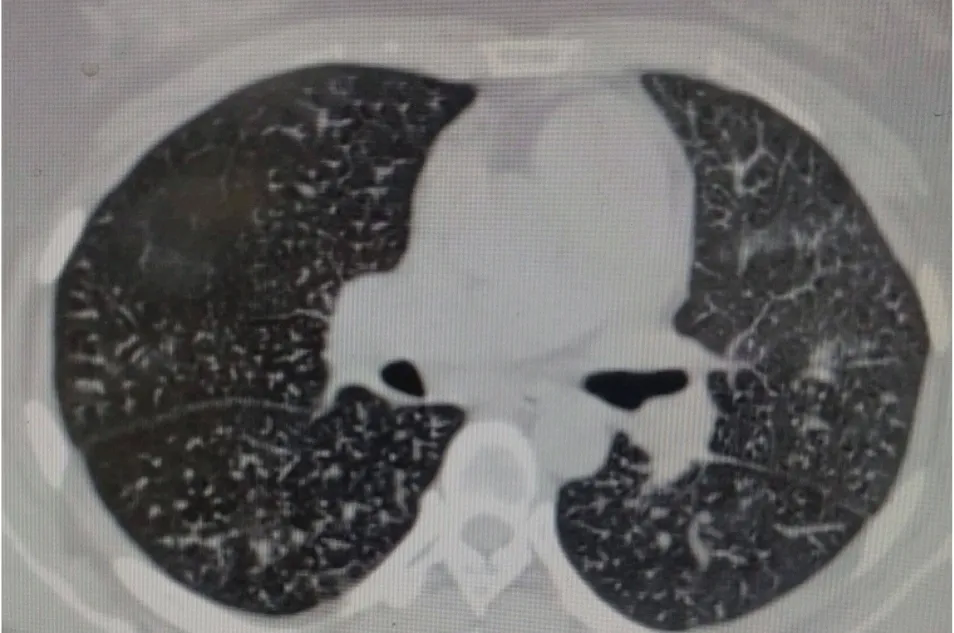

入院后,主管医生孙昉昉副主任医师尽快完善相关检查,血气分析提示氧分压62mmHg(正常人>80mmHg)。1月9日我院CT示:弥漫性粟粒样肺结节,以双下肺为主,伴有间质性炎症改变,肺动脉高压。心脏超声示:肺动脉高压,肺源性心脏病,少量心包积液。肺功能示:重度混合型肺通气功能障碍。

由于患者病情复杂,马战平主任组织科室进行疑难病例讨论。患者病情特点:一是病史1年余,主要表现为反复咳嗽,咳痰,气短,病情呈进展性,伴有痰中带血;二是有低氧血症,肺源性心脏病;三是肺功能示重度混合性肺通气功能障碍;四是影像学提示弥漫性粟粒状结节影,以中下肺为主,部分融合成纤维化,肺动脉高压。讨论结果考虑肺结节病或肺含铁血黄素沉着症可能性大,需要做气管镜以明确诊断。

特发性肺含铁血黄素沉着症是一种罕见的,发病原因不明的疾病,可能与遗传、环境、免疫、过敏等有关。临床以弥散性肺泡出血和继发性缺铁性贫血为特征,大量的含铁血黄素沉着于肺泡内,最终可发生肺间质纤维化。主要临床表现为发作性、进展性,反复咳嗽、咳痰、咯血、呼吸困难、乏力、消瘦;CT表现为双肺弥漫性斑片影,以双下肺为主;肺活检可见含铁血黄素颗粒。临床表现与肺出血程度密切相关。典型的三联征是反复咯血、缺铁性贫血、胸部影像呈弥漫性肺部浸润。该病的治疗以糖皮质激素、免疫抑制剂为主。病情预后因人而异,尽早控制急性发作、减少急性发作次数是改善预后的关键。